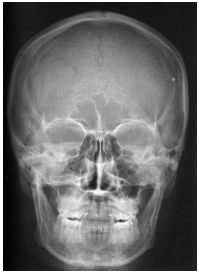

Analise as radiografias da face abaixo e marque a alternativa que contém o nome das incidências correspondentes.

01 -

02 -